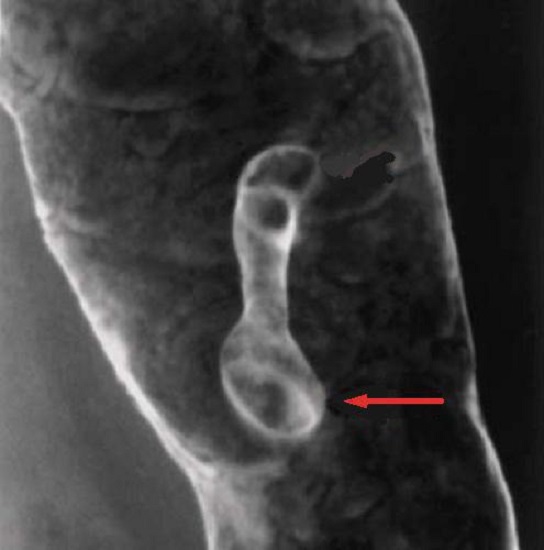

Aspect du polyp du colon en

lavement baryte a double de contrast . La polyp

situe en face anterieure du colon et intraluminale

avec de long pedicule . Aspect etre ressemble d'une diverticule du colon

. |